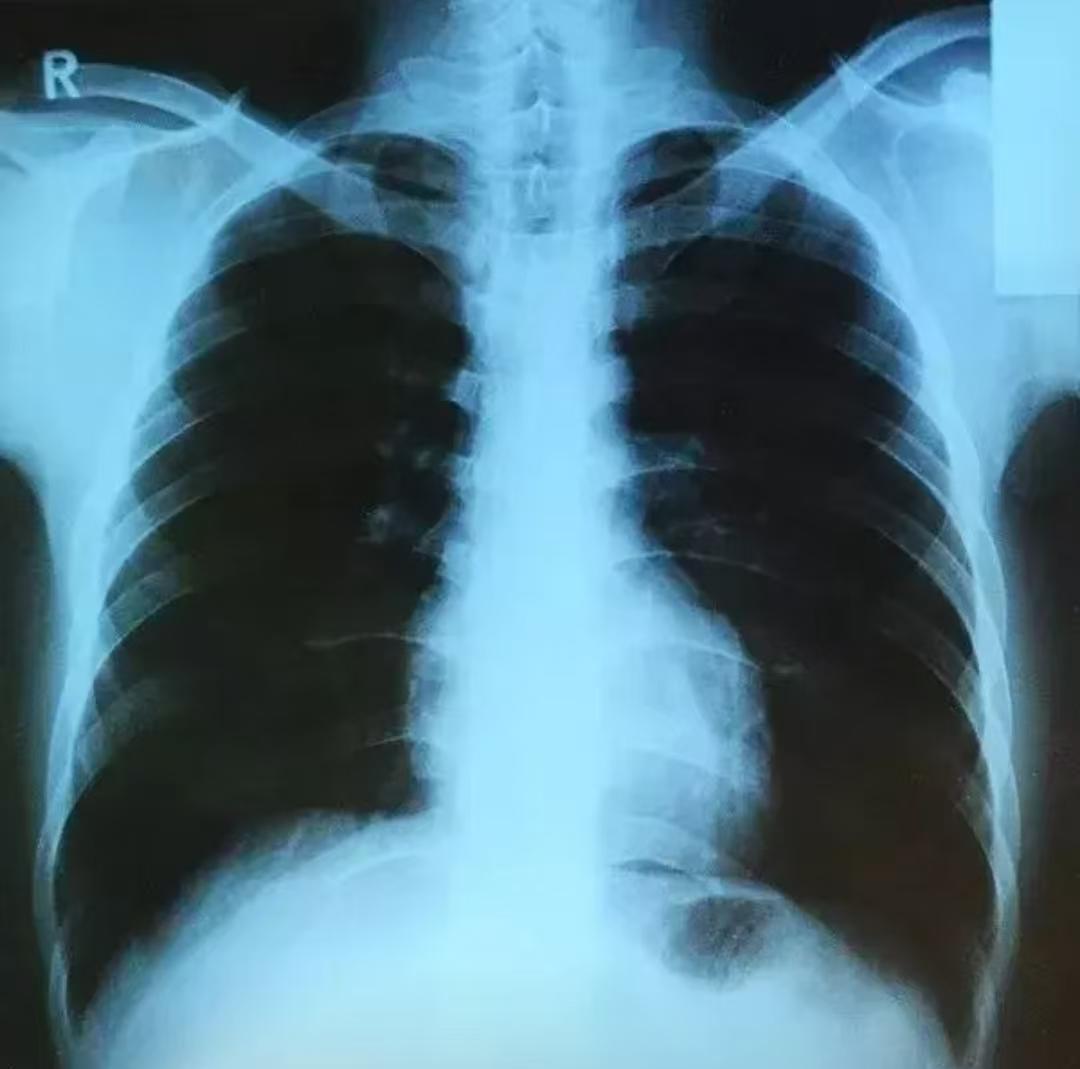

CT越来越先进了,今后的CT检查不仅能清晰看到2mm以下的肺结节以及人体肺部最小的功能区 “ 次级肺小叶 ”,还能将辐射降低60%-80%,大大提升了检查的准确度和安全性。 由中国企业纳米维景自主研发的 “ 相控阵 ”CT目前已在上海瑞金医院安装启用,估计在今年年底前会获批并进入小批量生产阶段,生产出来后会率先运用于三甲医院。 那么“ 相控阵 ”CT比起传统的CT检查到底有哪些优势呢? 1.扫描速度更快。传统的CT完成全身的扫描大概需要10-20秒左右,而相控阵CT仅需0.1-0.3秒左右就能冻结动态器官运动状态,使动态器官清晰成像。 2.图像的分辨率更高。相控阵CT的分辨率比我们平时所做的普通CT提高了64倍,它可以更清晰地显示肺结节的大小、形态、边界和内部结构比如是否钙化、空泡及与周围血管的关系,提升良恶性初步判断的准确性。 3.电离辐射降低。相控阵CT通过探测器高效捕捉信号,而传统的CT检查是通过发射X射线穿透人体,再根据射线的吸收差异生成的图像,所以相控阵CT的辐射量可降低60%-80%,单次检查的辐射量可低至1-3毫西弗,相当于1年内人们受到的天然辐射量,极大提升了检查的安全性。 4.诊断的准确性更高。相控阵CT可以提供更详细的图像信息,帮助医生更早更准确地发现病变,例如在肺部筛查中能清楚地呈现了2mm以下的微小结节及周边的血管细节,在骨科手术中,能提供类似于显微镜下的骨骼结构信息。 所以相控阵CT普及后,能帮助人们减少不必要的重复CT和肺结节的穿刺活检,既节省了医疗开支,也减少了人们的痛苦,让患者受益。